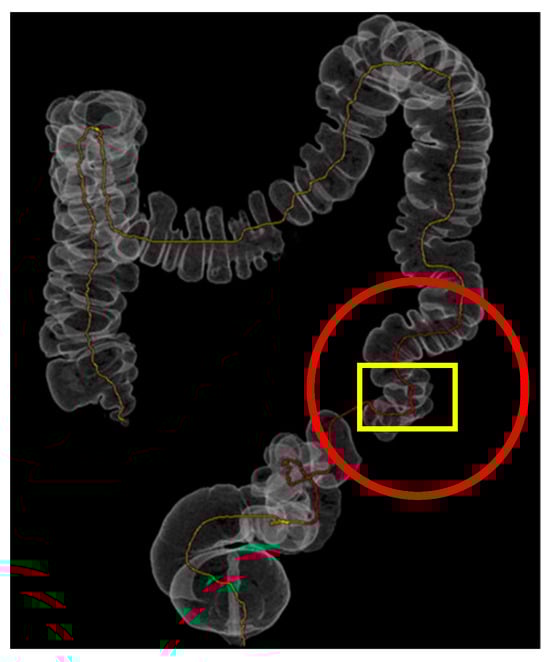

| Feature Evaluated | Virtual Colonoscopy Findings | 3D-Printed Model Findings |

|---|---|---|

| Extent of diverticulosis | Massive diverticulosis of sigmoid and descending colon | Same finding confirmed with clearer visualization of segmental involvement |

| Stenotic area | Suspected narrowing, poorly defined | Stenotic segment clearly delineated, with precise localization and extension |

| Anatomical relationships | Limited perception of spatial relations | Improved understanding of relationship between diseased colon and surrounding structures |

| Surgical planning implications | Suggestive of need for resection | Supported decision for left hemicolectomy |

| Tactile/spatial perception | 2D visualization only | Physical 3D model provided tactile and spatial feedback useful for team discussion and planning |